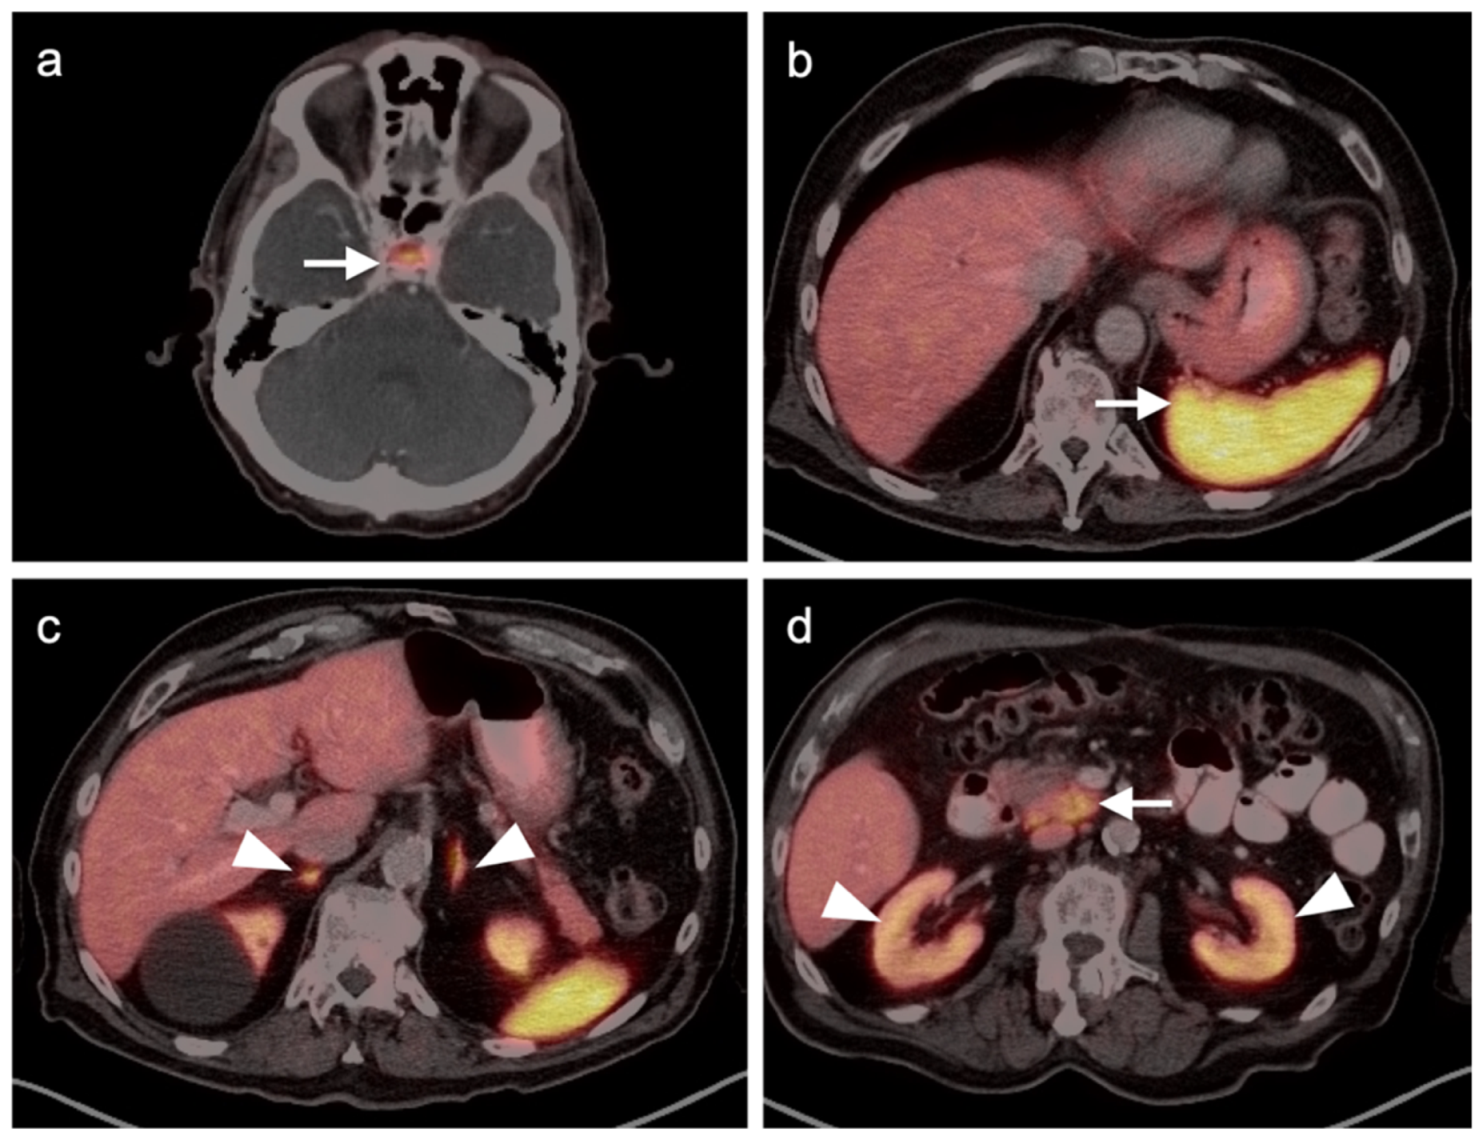

- Goerres, G.W.; Stoeckli, S.J.; Von Schulthess, G.K.; Steinert, H.C. FDG PET for Mucosal Malignant Melanoma of the Head and Neck. Laryngoscope 2002, 112, 381–385. [Google Scholar] [CrossRef]

- Murphy, G.; Hussey, D.; Metser, U. Non-cutaneous melanoma: Is there a role for18F-FDG PET-CT? Br. J. Radiol. 2014, 87, 20140324. [Google Scholar] [CrossRef] [Green Version]

- Falch, C.; Mueller, S.; Kirschniak, A.; Braun, M.; Koenigsrainer, A.; Klumpp, B. Anorectal malignant melanoma: Curative abdominoperineal resection: Patient selection with 18F-FDG-PET/CT. World J. Surg. Oncol. 2016, 14, 185. [Google Scholar] [CrossRef] [Green Version]